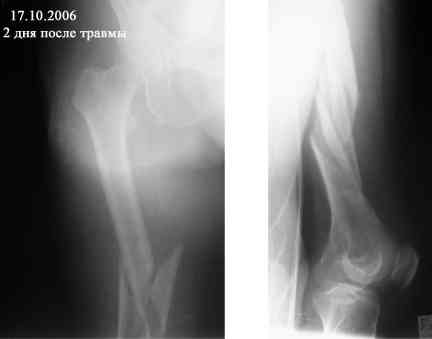

В продолжение темы оскольчатого перелома бедренной кости.

Р-граммы в динамике